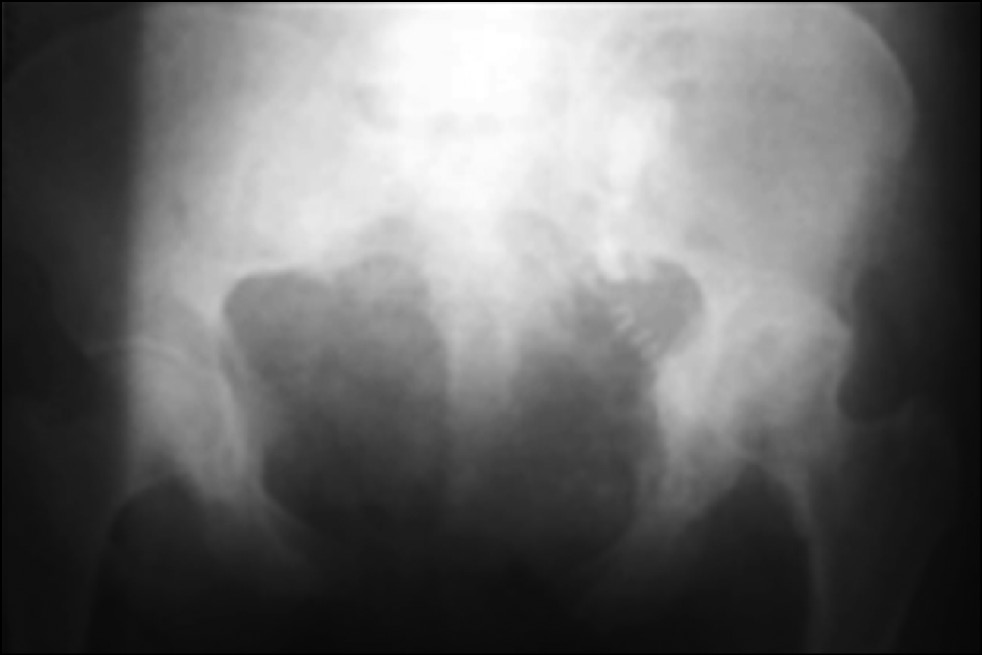

Клинический пример № 2. Пациентка, 53 года, поступила через 4 нед. после кататравмы с диагнозом: «Последствия тяжелой сочетанной травмы. Застарелый разрыв лобкового симфиза и крестцово-подвздошных сочленений с обеих сторон. Застарелый перелом левой лонной и седалищной костей, левой вертлужной впадины. Вертикальное смещение левой половины таза» (рис. 4).

Рис. 4. Обзорная рентгенография таза

Fig. 4. Plain radiography of the pelvis

Пациентке проведена компьютерная томография таза (рис. 5).

Рис. 5. Компьютерная томография таза

Fig. 5. Computed tomography of the pelvis